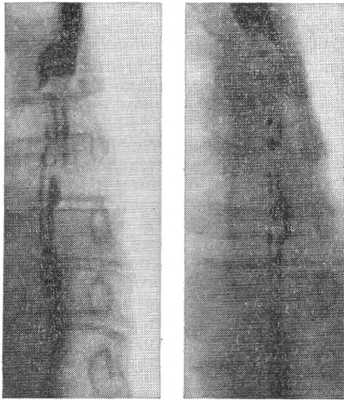

Синдром Баршоня — Тешендорфа: изменчивость рентгенологической картины пищевода (снимки сделаны с интервалом в 15 мин.).

Диагностика возможна лишь с помощью контрастного рентгенологического исследования, при котором определяется характерный четкообразный вид пищевода. Участки пищевода, расположенные между двумя соседними спастически сокращенными отрезками, могут иметь округлую, овоидную или неправильную косую форму. Нередко можно наблюдать спонтанное расправление спазмированных участков пищевода или перемещение их в каудальном направлении; в других случаях рентгеновская картина длительное время остается стабильной.

Применение атропина, папаверина, метацина, нитритов приводит к временному ослаблению или исчезновению спазмов и восстановлению проходимости пищевода. Изменчивость рентгенологической картины (рис.), а также реакция на указанные препараты позволяют правильно провести дифференциальную диагностику. В трудных для диагностики случаях может быть применена париетография пищевода (см. Париетография).